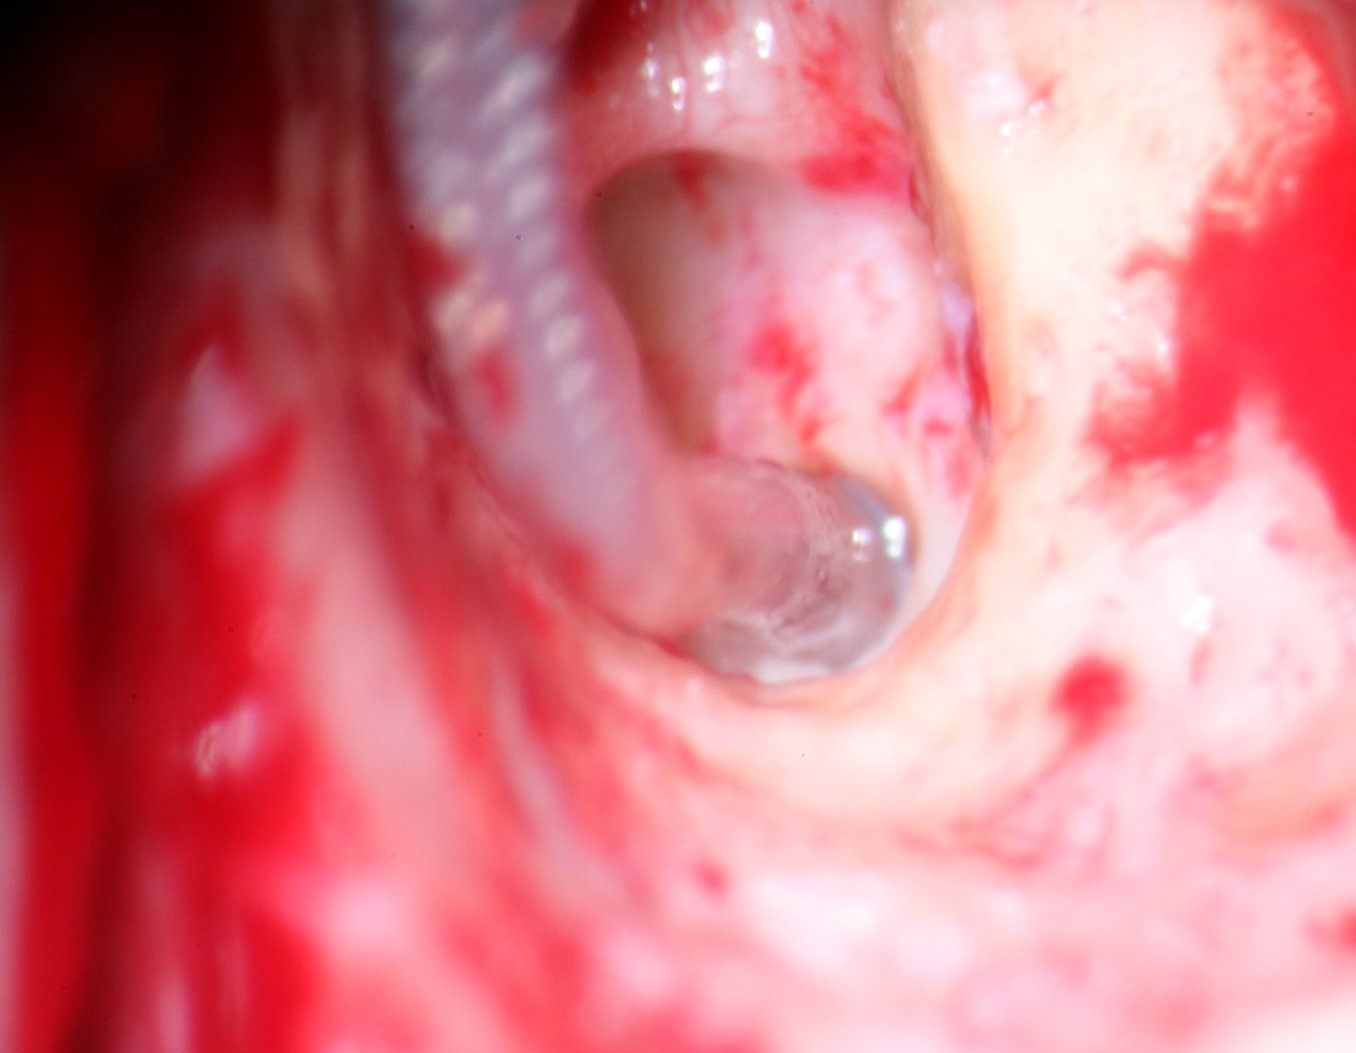

Abb: Dr. Keck bei der Durchführung einer Cochlea-Implantation

Ähnlich zum Mittelohrimplantat, wird in einer Operation in Vollnarkose eine Empfängerspule mit Elektrode in das Felsenbein eingesetzt und, im Unterschied zum Mittelohrimplantat, die Elektrode mit ihrem aktiven Ende in eine Öffnung der Hörschnecke eingeführt. Von außen muss wiederum eine Sendespule magnetisch aufgesetzt werden, die an einen Sprachprozessor angekoppelt ist.